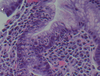

What is seen here?

Viral esophagitis (typical of herpes):

- Margination of chromatin

- Nuclear molding

- Multinucleate

Also ground glass appearance of nuclei and necroinflammatory debris (ulcer)